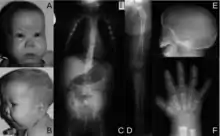

The ability of the Kozak sequence to optimize translation can result in novel initiation codons in the typically untranslated region of the 5′ (5′ UTR) end of the mRNA transcript. A G to A mutation was described by Bohlen et al. (2017) in a Kozak-like region in the SOX9 gene that created a new translation initiation codon in an out-of-frame open reading frame. The correct initiation codon was located in a region that did not match the Kozak consensus sequence as closely as the surrounding sequence of the new, upstream initiation site did, which resulted in reduced translation efficiency of functional SOX9 protein. The patient in whom this mutation was detected had developed acampomelic campomelic dysplasia, a developmental disorder that causes skeletal, reproductive and airway issues due to insufficient SOX9 expression.[32]